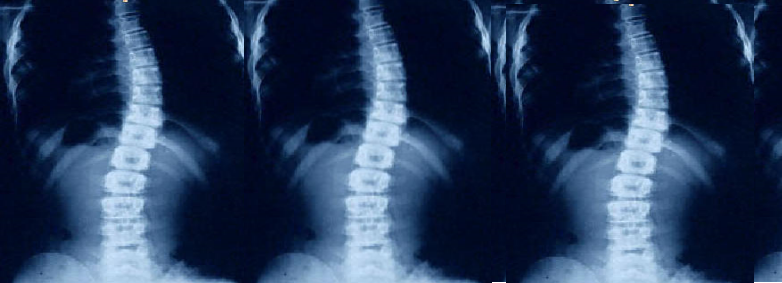

A Coluna Vertebral e as Suas Curvas

Escoliose idiopática. Raio x frontal . Na radiografia podem observar-se : anomalias vertebrais e costais, número de vértebras, padrão de curva, vérteb...